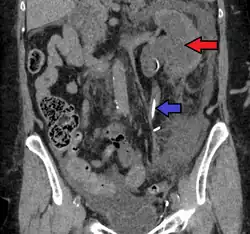

Left sided hydronephrosis in a person with an atrophic right kidney. Stent is also present (image below).

Left sided hydronephrosis, coronal view. Stent is also present.

Treatment of hydronephrosis focuses on the removal of the obstruction and drainage of the urine that has accumulated behind the obstruction. Therefore, the specific treatment depends upon where the obstruction lies.[14]

Acute obstruction of the upper urinary tract is usually treated by the insertion of a nephrostomy tube. Chronic upper urinary tract obstruction is treated by the insertion of a ureteric stent or a pyeloplasty.[13]